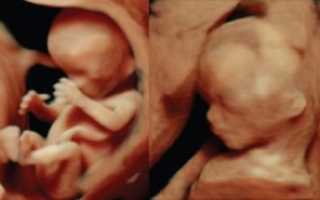

Скрининг. УЗИ 12 недель беременности — плановое исследование, которое проводится в конце 1 триместра.

Вместе с УЗИ женщина сдает кровь на биохимический анализ, чтобы исключить риски неправильного развития плода, тонус матки и генетические заболевания. Такие исследования не опасны для малыша, если делать их в установленные даты.

Зато они очень информативны, поэтому игнорировать их не стоит. Приятный бонус исследования — ты узнаешь пол своего малыша.

Прогрессирующая беременность, развивающаяся в маточной полости подтверждается результатами УЗИ – трансабдоминальное и вагинальное. Вагинальный способ применяется на сроке не более 10 недель.

Что видно в УЗ аппарат:

• расположение желтого тела;

• наличие/отсутствие плодного яйца и его место нахождения;

• помимо этого: строение и эхогенность яичников, строение полости матки, миома (если имеется) и кисты (если имеются).

УЗ диагностика стопроцентно подтверждает, прогрессирует ли беременность, и к какому виду она принадлежит.

Исследование позволяет также выявить аномальное развитие плода на ранних сроках.